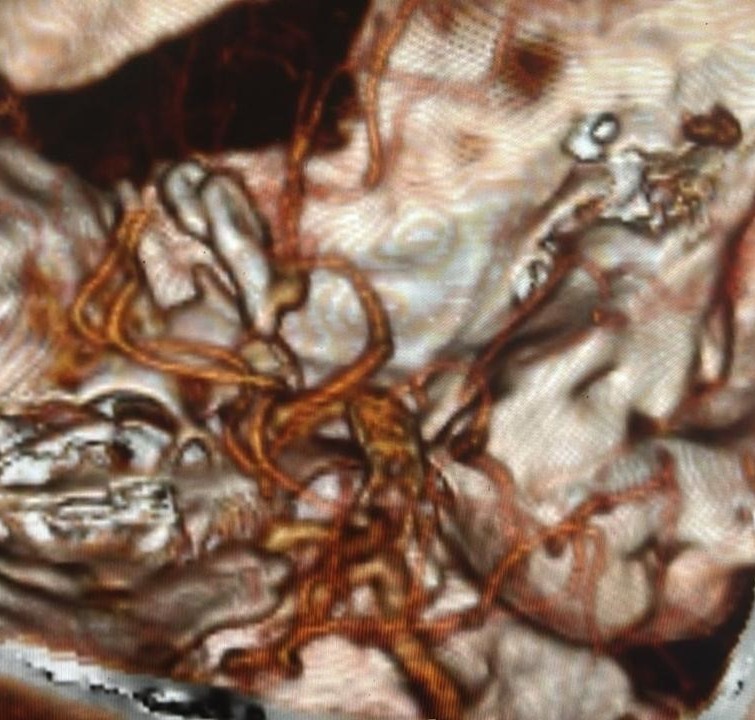

Non-contrast computed tomography (NCCT) of the brain revealed subarachnoid hemorrhage predominantly in the right sylvian fissure [Figure 1]. Hemorrhage grading scales indicated: Modified Fischer Scale 1, Classen Scale 1, and Hijdra Scale 0; indicating minimal blood burden with low risk for delayed cerebral ischemia and vasospasm. These favourable grading parameters not only suggested minimal vasospasm risk but also projected good functional prognosis.

Computed tomography angiography (CTA) revealed an anomalous saccular aneurysm (7×5 mm) arising from the M1 segment of the right middle cerebral artery [Figure 2]. This finding was unusual as the branching artery demonstrated characteristics consistent with orbitofrontal artery territory supply. Digital subtraction angiography (DSA) performed via right femoral approach using a JR 3.5 5F guide catheter confirmed a Type 3 aortic arch with the anomalous aneurysm location [Figure 3]. The aneurysm demonstrated a broad neck and favorable morphology for microsurgical intervention.